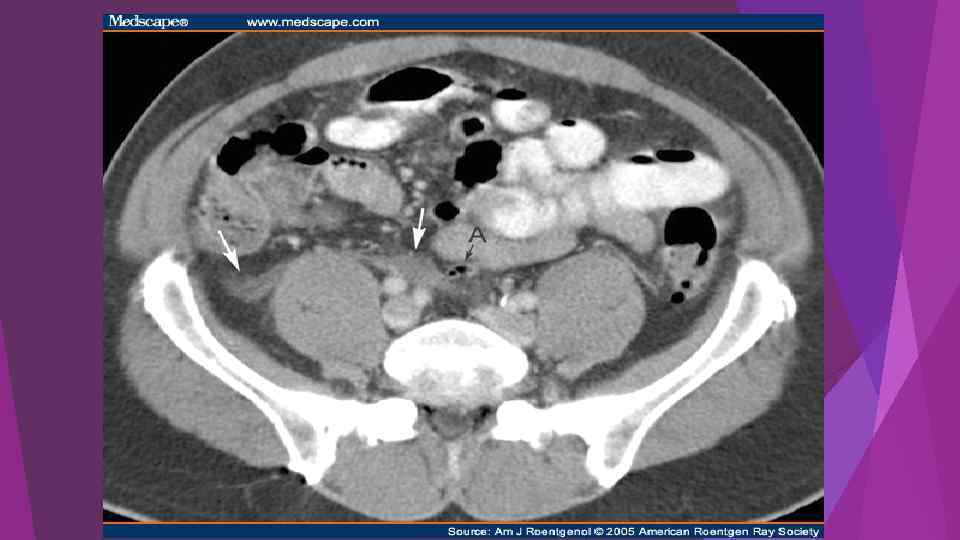

Acute pancreatitis and pseudocyst. A 63 -year old woman admitted with gallstonerelated pancreatitis.

Acute pancreatitis and pseudocyst. A 63 -year old woman admitted with gallstonerelated pancreatitis.